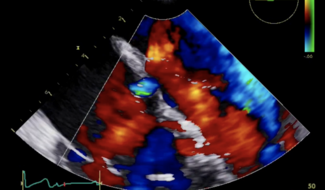

Marco Toselli, MD; Alessandro Sticchi, MD; Kailash Garhwal, MD; Angelo Squeri, MD; Antonio Colombo, MD; Francesco Giannini, MD

We report the case of a 78-year-old female patient with a history of atrial fibrillation and severe isolated TR in New York Heart Association functional classification III despite optimal medical therapy. This case illustrates immediate and...